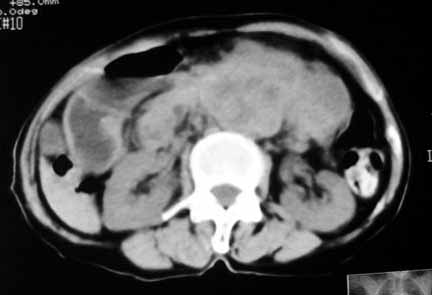

1.中腹部腹主动脉旁可见巨大包块影,其形态似为2个(或分叶),与腹主动脉分界不清,边界较清,其内密度不均匀(稍高、不匀称低密度),腹膜后未见确切肿大淋巴结...性质?考虑腹主动脉瘤可能性大,不排除平滑肌瘤及畸胎瘤可能,建议增强ct;

3.右肾前外极囊性低密度影,边界清楚,考虑肾囊肿可能。

考虑:1、左侧腹膜后占位性病变(以间叶源性肿瘤可能性大);

脂肪肉瘤,平滑肌肉瘤的可能性大。支持!(本例关键是定位,仔细分析,可以观察到主动脉被包埋于肿瘤内,因此可定位于—来源于腹膜后的实性肿瘤。)

腹膜后肿块侵犯腹主动脉及肠系膜上动脉,肿块密度不均,1来源间叶组织肿瘤,2肠系膜恶性肿瘤可能大,

腹膜后占位性病变,腹膜后淋巴结转移,脾门动脉硬化,右肾囊肿。